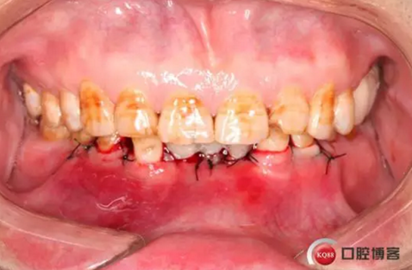

下圖是術后照片 治療過程 術前測量上下牙長度比例,確定水激光冠延長深度約3mm,拔除31、41,在術區(qū)減低牙槽嵴高度,32、42位點種植MINI型一段式種植體,使用臨時愈合帽行暫時性修復。

治療前后照片顯示患者上下臨床牙冠比例協(xié)調(diào),患者對臨時修復體效果十分滿意。當然有待后期愈合及長期的臨床隨訪,以觀察遠期臨床效果。將水激光應用臨床冠延長,有利于精準去除骨量,利于術后愈合。而MINI型一段式種植體滿足骨寬度不足,及臨時修復打下堅實基礎。